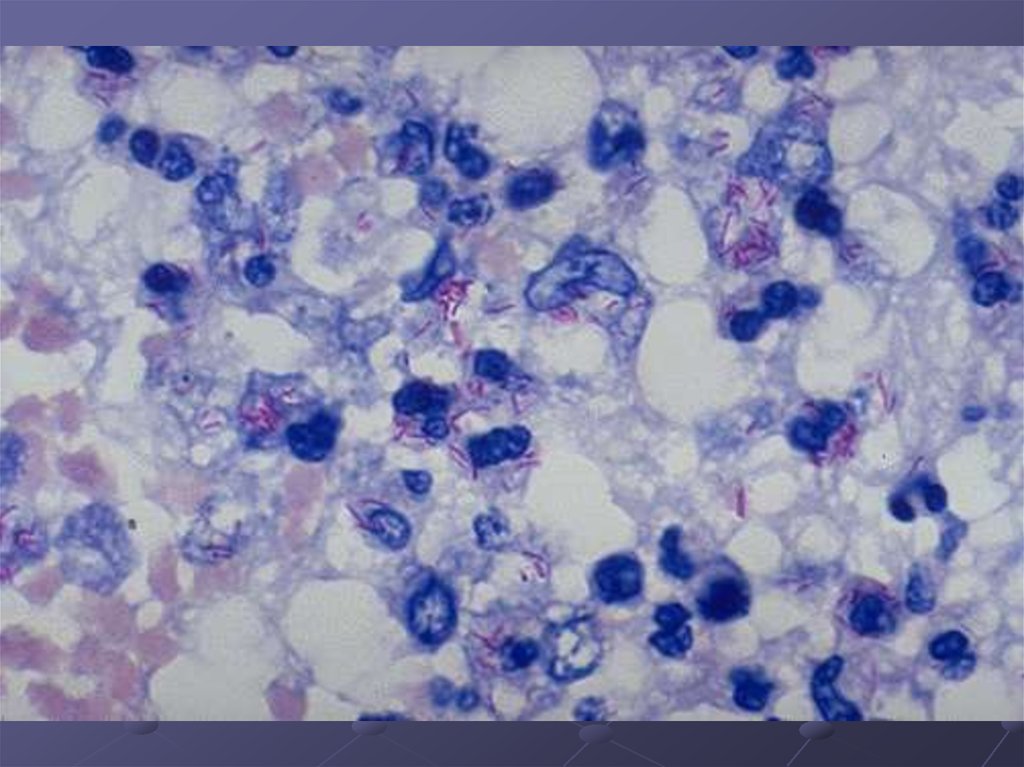

БАКТЕРИОСКОПИЧЕСКИЙ

окраска по ЦилюНильсену

люминесцентная

микроскопия